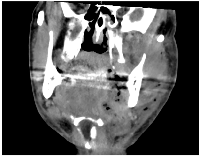

Early diagnosis is key to reducing mortality. Clinical suspicion should be confirmed with contrast-enhanced computed tomography (CT), which typically reveals fascial thickening, gas formation, and fluid collections along fascial planes [12, 13] (Figures 1 and 2). In some cases, magnetic resonance imaging (MRI) may offer higher soft tissue resolution, but its availability and speed are limiting factors in the acute setting [14]. Laboratory findings typically include elevated white blood cell counts, C-reactive protein (CRP), creatine kinase (CK), and lactate levels [15]. The Laboratory Risk Indicator for Necrotizing Fasciitis (LRINEC) score has been proposed as a diagnostic aid but has limited sensitivity in cervicofacial cases [16]. Several factors contribute to the reduced diagnostic utility of LRINEC in the head and neck region. First, gas-forming organisms, such as Clostridium spp., are less commonly involved in CNF than in infections of the trunk or limbs, which lowers the incidence of radiologically visible emphysema and correlating inflammatory patterns. Second, smaller anatomical compartments in the head and neck region may limit the extent of tissue destruction and systemic inflammatory response, particularly in the early stages—resulting in lower CRP, WBC, or creatinine values and thus underestimating LRINEC scores.